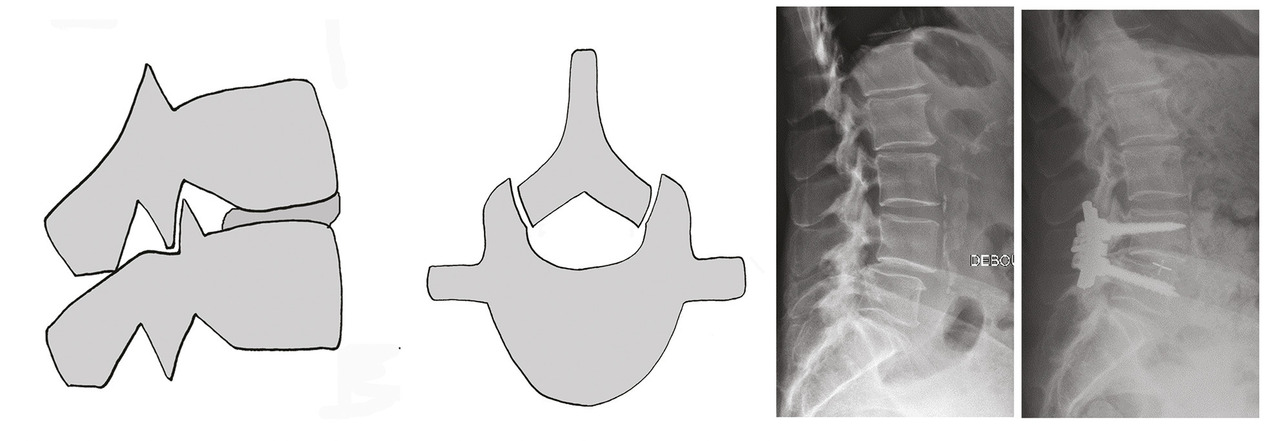

L’ostéosynthèse moderne permet de fixer solidement le rachis. Les vis pédiculaires,5 au besoin aidées par le cimentage du corps vertébral, sont utilisées couramment dans tous les services de chirurgie du rachis. L’immobilité obtenue est le meilleur moyen de lutter contre la douleur.6 Mais l’ostéosynthèse permet aussi la réduction de la déformation dans les trois plans de l’espace (fig. 3 et 4 ). L’équilibre rachidien restitué facilite la reprise de la marche et redonne une vie plus facile au patient qui a subi dans son dos le poids des ans.7 L’ostéosynthèse est solide et permet un lever immédiat en règle générale sans contention externe. Une greffe osseuse pérennise le montage le protégeant d’un démontage ou d’une fracture du matériel.

L’ostéosynthèse moderne permet de fixer solidement le rachis. Les vis pédiculaires,5 au besoin aidées par le cimentage du corps vertébral, sont utilisées couramment dans tous les services de chirurgie du rachis. L’immobilité obtenue est le meilleur moyen de lutter contre la douleur.6 Mais l’ostéosynthèse permet aussi la réduction de la déformation dans les trois plans de l’espace (